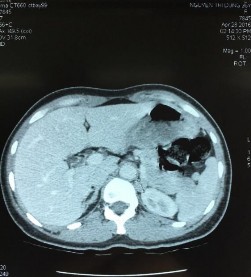

Ảnh bệnh phẩm và hình ảnh học.

Phim CT scan bướu tuyến vỏ thượng thận bên trái

[Nguyễn Thị D., 36 tuổi, SNV: 2160043235]